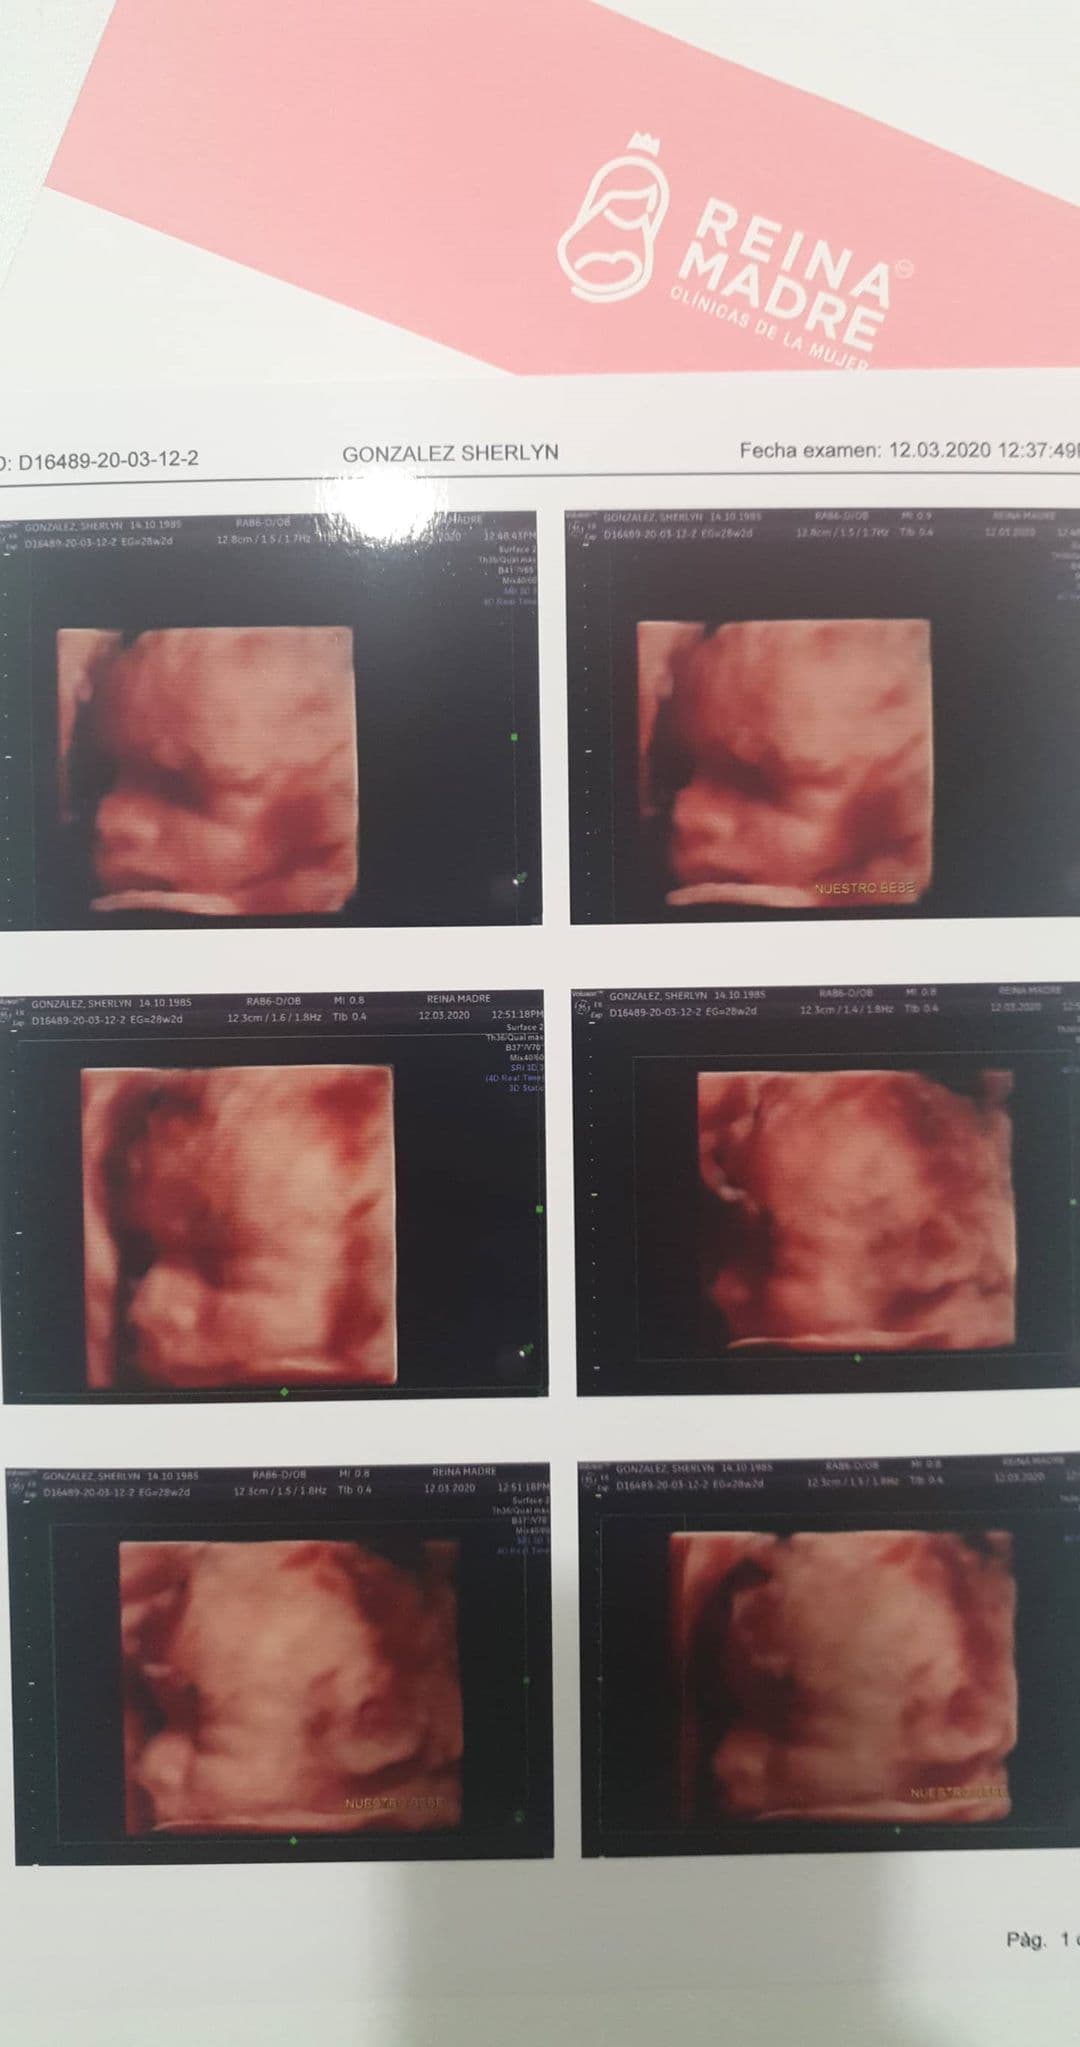

La actriz mostró imágenes del último ultrasonido que le hicieron en el que se observa a la perfección el rostro del bebé

Fue a través de su cuenta oficial de Instagram que la conductora del programa Hoy compartió una serie de imágenes del reciente estudio que le hicieron con 28 semanas de gestación y en ellas se alcanza a percibir a la perfección los rasgos faciales de su primogénito.